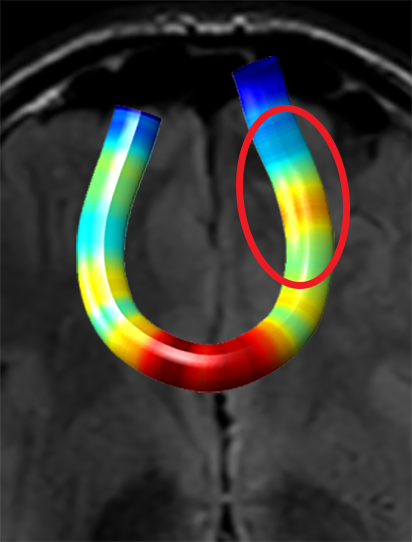

We performed pairwise comparison between two scans of a 32-year-old basketball player, diagnosed with mild occipital traumatic brain injury and frontal hemorrhage due to contrecoup impact, acquired one week and 6 months post-injury. The hemorrhagic lesion at the frontal right hemisphere of the player is no longer visible in the FLAIR image acquired 6 months after injury (Fig. 2a). Local differences between corresponding, longitudinal FA- and MD-FFDD profiles of the FMT (chosen due to its proximity to the lesion area) are shown in Fig. 2d. Figs. 2b-c present color-coded FMT to visually demonstrate these differences. Results show significant longitudinal variability at the right hemisphere part of the tract, corresponding to the lesion area, and relatively minor differences along the rest of the tract. These results should be considered as a proof of concept, validating the FFDD analysis results for the detection and localization of mTBI-related variabilities between fiber bundles.

| ONE WEEK | ![]() |

![]() |

FA-FFDD |

| 6 MONTHS | ![]() |

MD-FFDD |

| (a) FLAIR | (b) FA-FFDD | (c) MD-FFDD | (d) Local Differences |